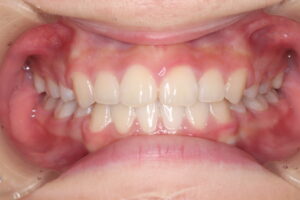

患者さんは、上下の前歯が強く突出しており、横顔を気にして来院されました。

診断の結果、口唇突出を伴う上下顎前突(skeletal2)

治療内容:

上顎左右第一小臼歯、下顎両側第二小臼歯(計4本)を抜歯

上裏側、下表側のブラケット装置で治療

治療期間は2年11ヶ月

結果:

口元の突出感が大きく改善